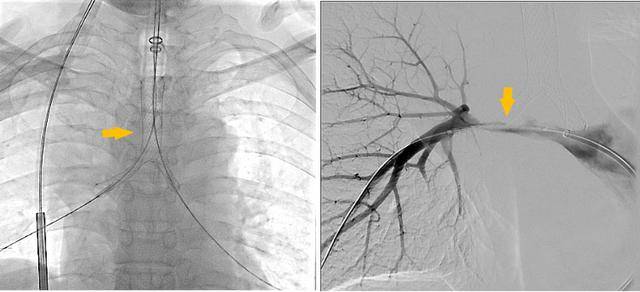

同期置入支架后狭窄明显改善

重生:从呼吸困难到畅快呼吸

术后李先生的喘憋症状显著缓解:“那种窒息的恐惧感消失了,我终于能躺下睡个安稳觉了。”为平稳度过危险期,李大爷转至重症医学科接受高级别生命支持与治疗。经过短暂的术后观察,李先生各项生命体征平稳,活动耐量明显改善,顺利出院。